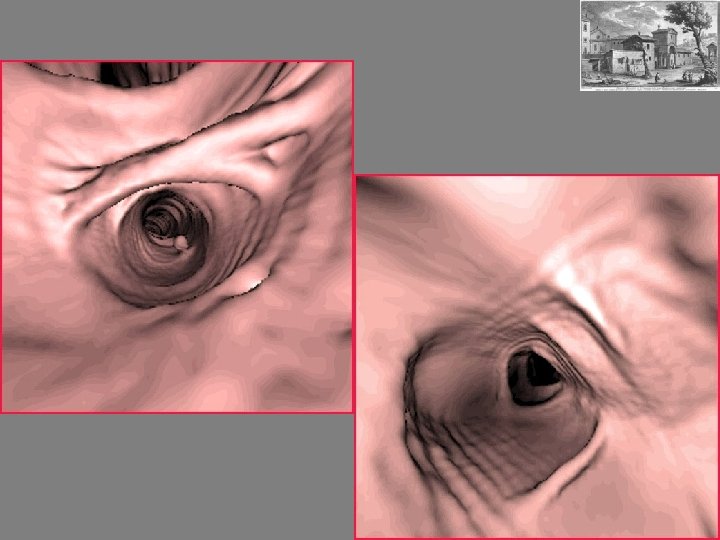

COLONSCOPIA VIRTUALE REFERTAZIONE - Ricostruzione delle immagini su diversi piani - Navigazione su workstation dedicate (CAD COLON) - Identificazione lesioni pre-cancerose(polipi >6 mm ) e cancerose - Valutazione organi addominali nelle sole condizioni basali

WORKSTATIONS